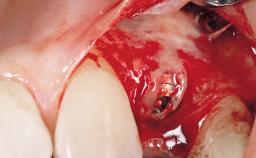

Immediate Flapless Placement of an Implant in a Maxillary Left Central Incisor Site

Placement Protocol Immediate implant placement

Socket Integrity Damage to one or more bone walls

Bone Volume Damage to one or more socket walls